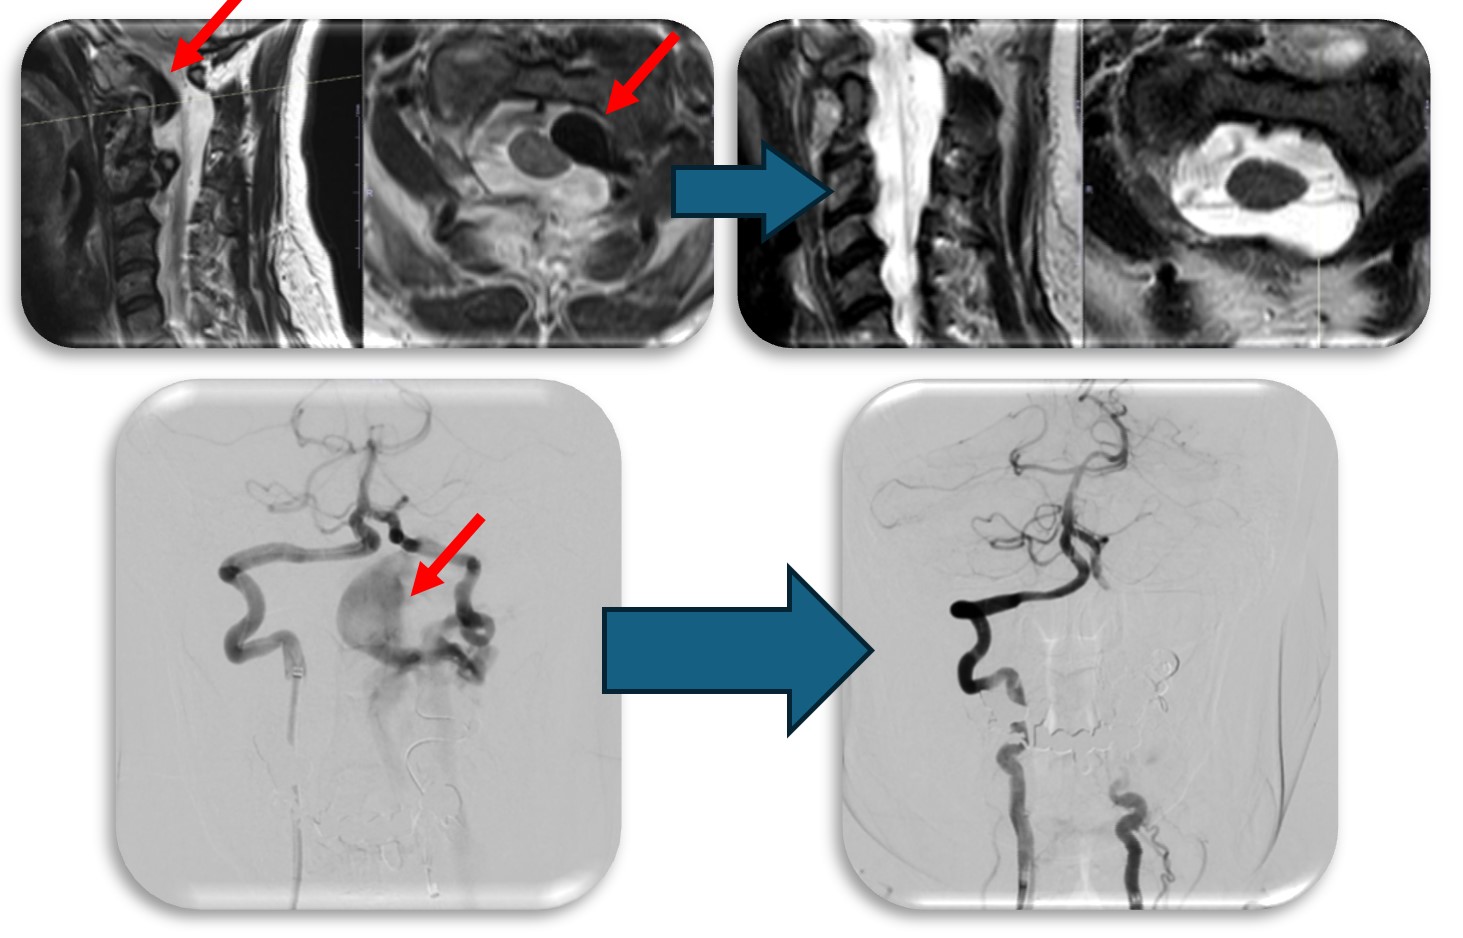

(代表例①)

硬膜動静脈瘻の症例です。脊髄血管奇形の中では最も多い疾患です。脊髄の静脈に動脈血流が直接流入する事により脊髄浮腫をきたし(赤矢印)、様々な神経症状が出ます。最近では血管内から治療することもありますが根治率は20%程度と非常に低く、基本的には高い確率で根治できる外科的治療を施します。当院では基本的には外科的治療を選択しますが、高齢者や外科的治療が困難な症例では血管内治療を検討することもあります。手術では動脈から静脈に直接流入する部位(緑矢印)を焼灼離断します。術直後に脊髄浮腫は改善し、造影CT検査で描出の認めた異常血管影(青矢印)は術後に消失しました。